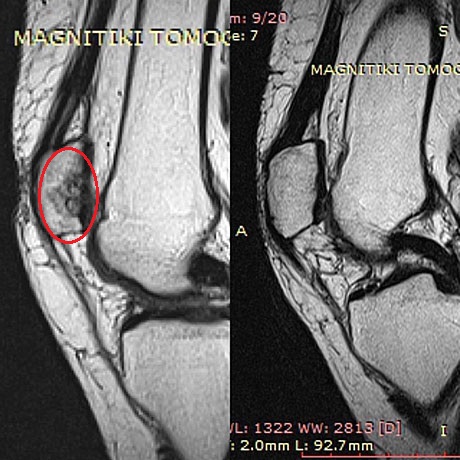

Woman 59 years old with severe damage of the patellar articular cartilage. Autologous bone marrow stem cells with collagen (AMIC technique), before and two years postop

The same patient.